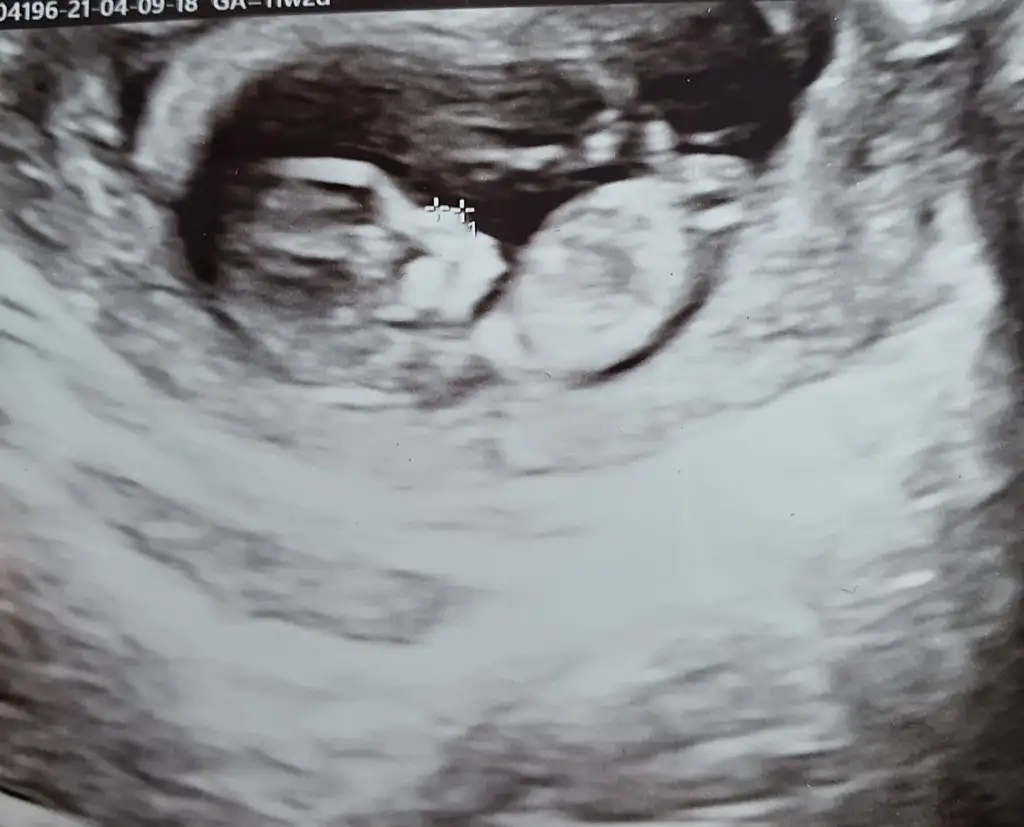

dr soylemeden siz gorun genital nub teorisi ( bebegin cinsiyeti)

Ikra meyra Ikra meyra canim 12+2 bı tahmin de bulunurmusun.İlk bebeğimi bilmistin ya.bunada yorum yaparsan sevinirim.tesekkurler .

Ikra meyra Ikra meyra 12+1 sata göre bana da bakar mısınız çok hareketli oldugu için bişey demedi Dr

Ikra meyra Ikra meyra 11 haftalik bana da tahmin de bulunurmusunuz nub tam olarak neresi ben pek anlamadim :)

Eklentiler

• BeautyPlus_20210409151800057_save.webp

BeautyPlus_20210409151800057_save.webp

28,1 KB · Görüntüleme: 64

• Screenshot_20210409-162230_Video Player.webp

Screenshot_20210409-162230_Video Player.webp

27,9 KB · Görüntüleme: 66